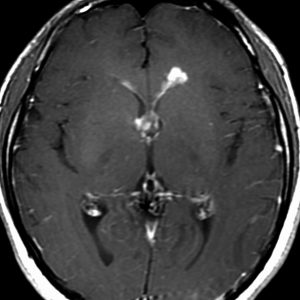

ガドリニウム増強では,前頭葉腫瘍というより,側脳室壁にベトベトくっついているような腫瘍です。germinoma特有のsubependymal infiltration像を示します。

左はICE化学療法 (IFO/CDDP/VP-16)前,右は1コース終了後です。腫瘍は顕著に縮小してgerminomaとして普通の化学療法反応性を示します。また,松果体と下垂体には腫瘍はありません。